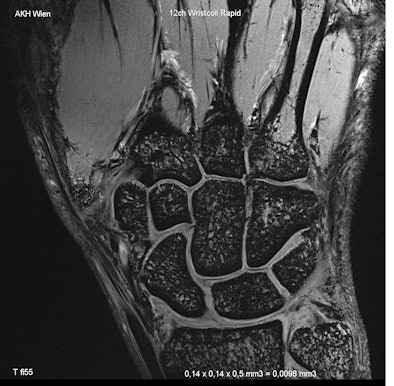

| High-resolution anatomical-morphological image of the wrist of a volunteer, during normal examination time at 7 tesla. (All images provided by Prof. Siegfried Trattnig) |

Apart from technical difficulties and adaptations that still need to be carried out before high-field imaging beyond 3.0 tesla becomes available for clinical use, both professors pointed out that there are already fields where the irrefutable benefits can be seen, but that it will still take time before patients can experience them first hand: "Imaging of smaller human body parts (leg, wrist, ankle, knee, or brain) is already possible on high-field MR systems with extraordinarily high image quality. I would expect clinical application of 7-tesla systems for special purposes (especially brain and joints) in the near future. But I am not sure whether high-field systems will replace standard imaging at 1.5 to 3.0 tesla within the next 10 years."